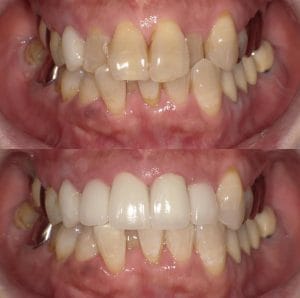

Case033

前歯が虫歯なのと、保険のプラスチックで大きく治療されていて色が悪いこと、歯並びが出っ歯気味であることを気にしてセラミックにしたいという主訴で来院された患者様です。

虫歯が大きかったところは神経治療をきちんと行い、

初診時を含めてトータル4回のご来院で完了です。

今回は前歯を下げる、歯列を整える、白すぎず自然に綺麗に見える色というご希望に沿って治療しました。

ご興味のある方はいつでもご相談ください。

担当 理事長 佐藤 悠野